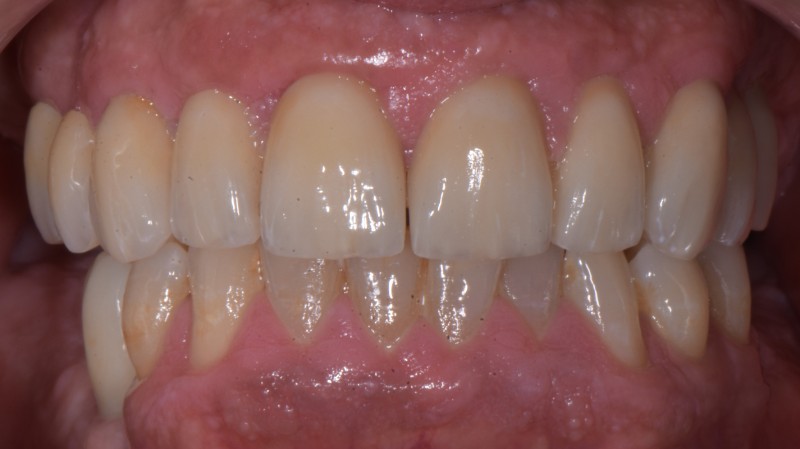

La Soluzione

Recupero conservativo dei denti recuperabili

Impianti in posizione 2.5 e 4. 5

Corone in ceramica sui denti superiori e sul 4.5

Ricostruzioni estetiche su 3.4 3.5 e 4.4

I Risultati

Paziente completamente recuperato dal punto di vista psicologico ora mantiene i risultati ottenuti con un' igiene più che soddisfacente. Son cose che fanno piacere.😊